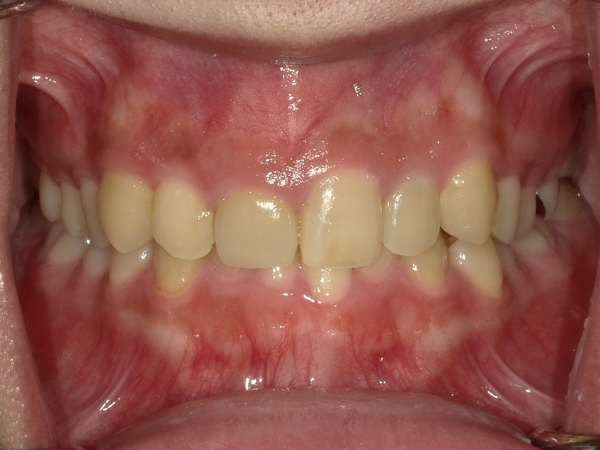

ガタガタとした歯並びや八重歯(叢生)CASE65